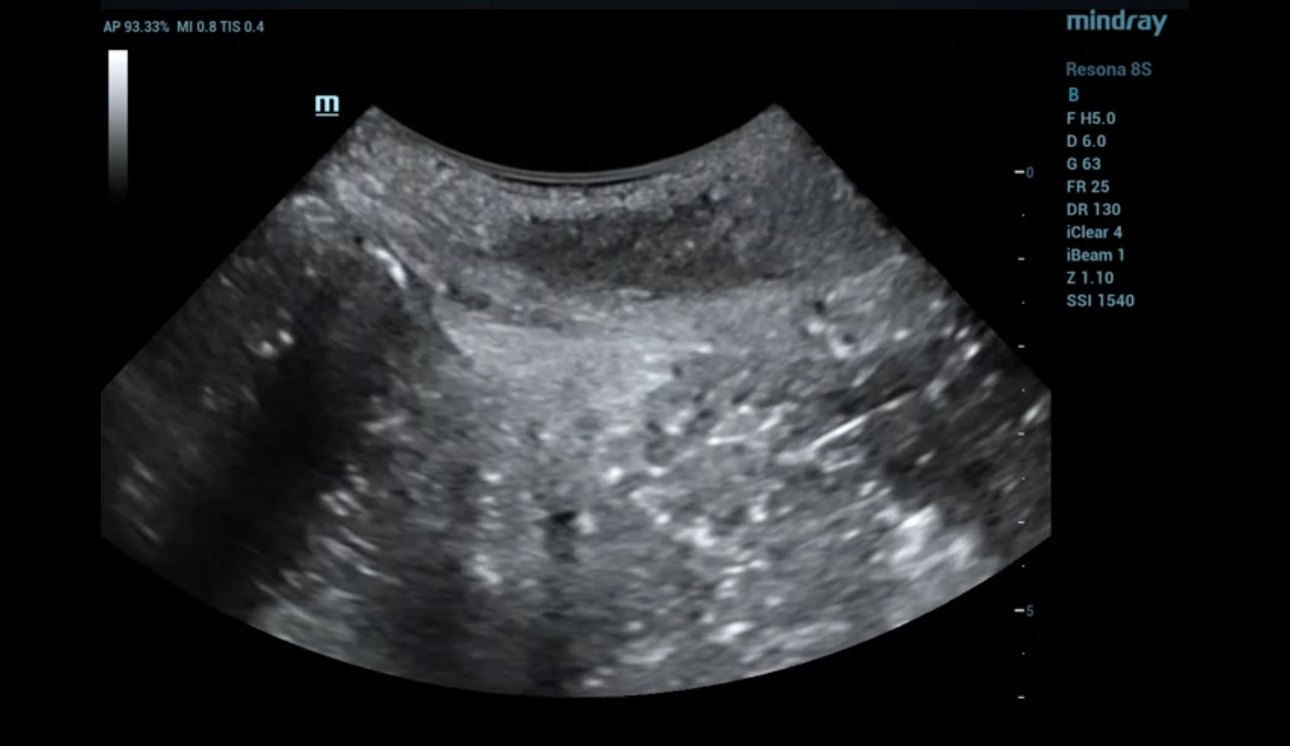

형상 5. 산후 9개월 이후 ipage+ 이미지

Video 4. 산후 9개월 review